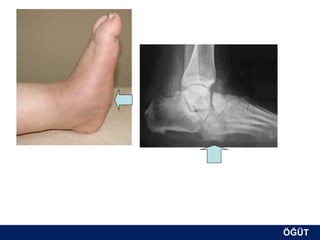

OLGU No 6

AT, 57 y, ♂

ÖĞÜT